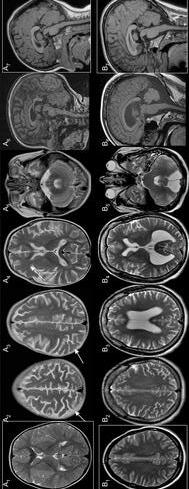

SCIENCE PLATFORMS ACTS OF KINDNESS RIPPLE EFFECT

2021, BRAIN MR PATTERNS IN NEUROTRANSMITTERS , ARTICLE

HELPER’S HIGH NEUROTRANSMITTERS

KINDNESS INCREASES

KINDNESS DECREASES

48